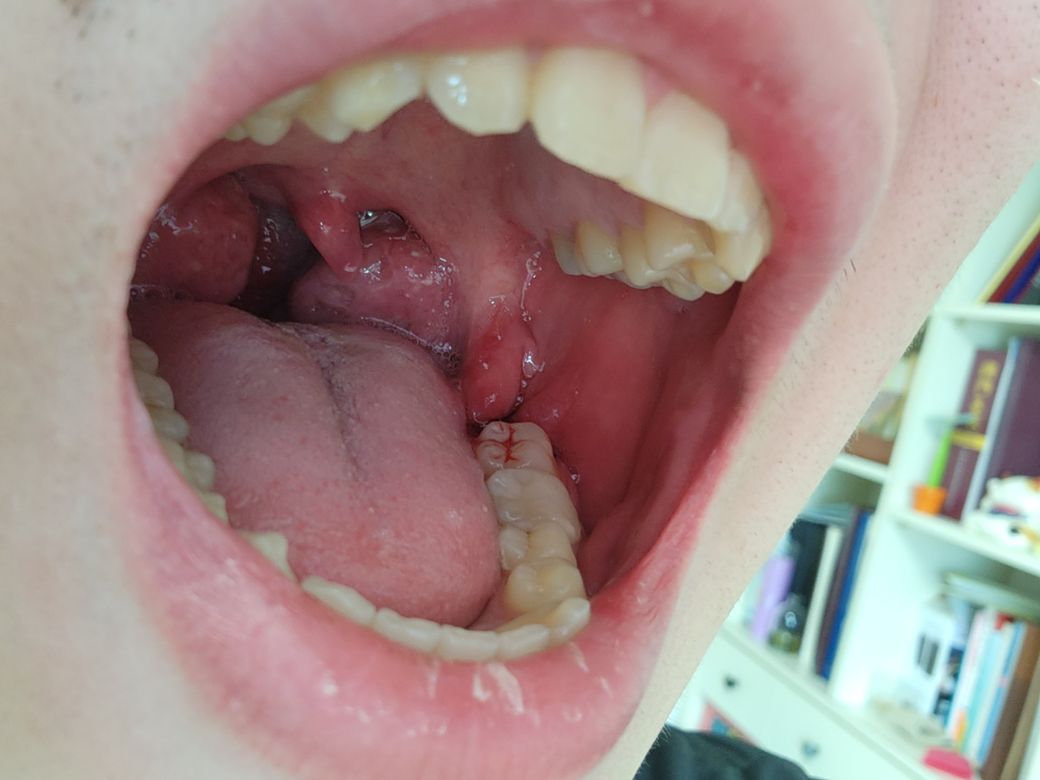

사랑니 이 정도면 지혈이 거의 다 되었다고 봐도 무방한가요?

• 오늘 10시 40분쯤에 발치는 끝났고 거즈를 꽉 물고 있다가 12시 38분쯤인가 뺐다가 한 5분뒤에 다시 물고 한 10분뒤에 마취가 풀려서 통증때문에 물기가 힘들어서 지금은 거즈가 없는 상태입니다. 혹시 다시 거즈를 물어야 하나요? 혀에 피 맛은 살짝 느껴집니다. 그리고 욱신거리는 거는 약 먹으면 가라앉겠죠?

네 지혈을 다 된것으로 보입니다.

다른 내용이지만 편도가 양쪽다 매우 큰편입니다.

사진으로는 심한 출혈은 없어보입니다.